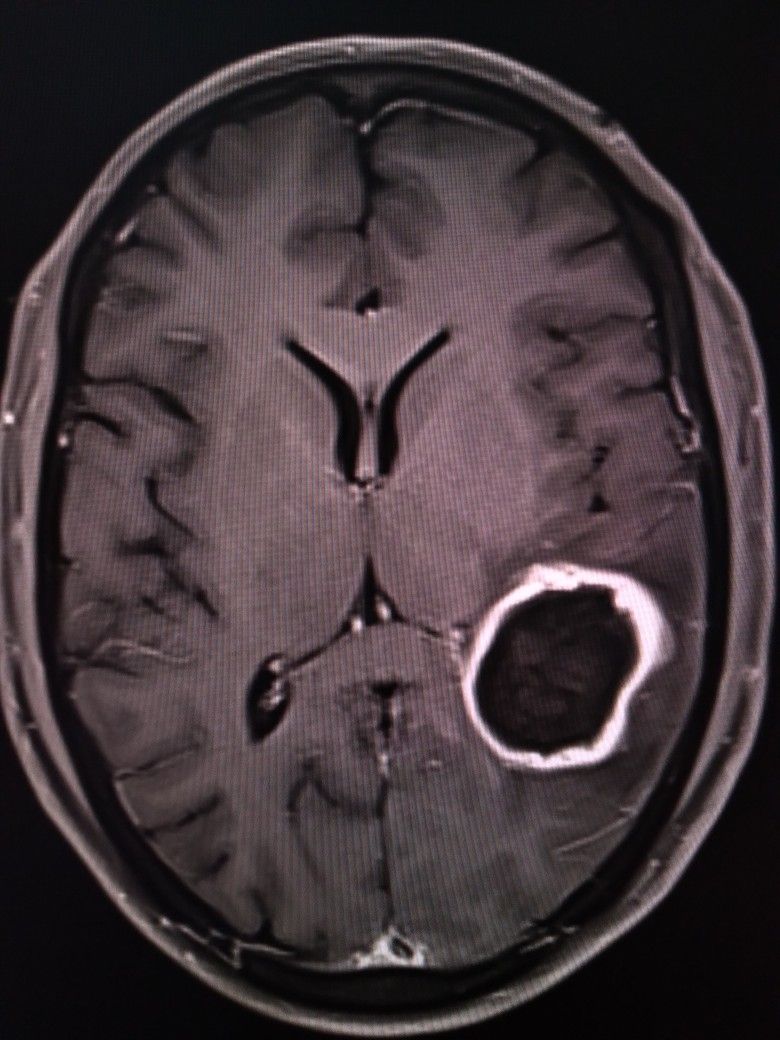

تشخیص آبسه مغزی از طریق روشهای تصویربرداری پیشرفته مانند سیتی اسکن (CT Scan) و امآرآی (MRI) مغز صورت میگیرد. درمان این بیماری یک فوریت پزشکی است و معمولاً شامل ترکیبی از آنتیبیوتیک درمانی و جراحی است.

۲. تخلیه با نوروناویشن (Aspiration with Neuronavigation)

در آبسههای بزرگتر از ۲.۵ سانتیمتر، یا مواردی که به درمان دارویی پاسخ نمیدهند، مداخله جراحی ضروری است. برای آبسههای عمقی و کوچک، روشهای با حداقل تهاجم (Minimally Invasive) ارجحیت دارند:

تخلیه سوزنی ساده (Simple Aspiration): در این روش، با استفاده از دستگاه نوروناویشن (Navigation) و سیتی اسکن برای تعیین موقعیت دقیق، یک سوراخ کوچک (Burr Hole) در جمجمه ایجاد شده و با یک سوزن (کانول)، چرک آبسه تخلیه میشود.

مزیت نوروناویشن: استفاده از دستگاههای ناوبری، بهویژه برای آبسههای واقع در عمق مغز، به جراح اجازه میدهد با دقت فوقالعاده بالایی مسیر سوزن را تعیین کرده و از آسیب به بافتهای حیاتی اطراف خودداری کند.